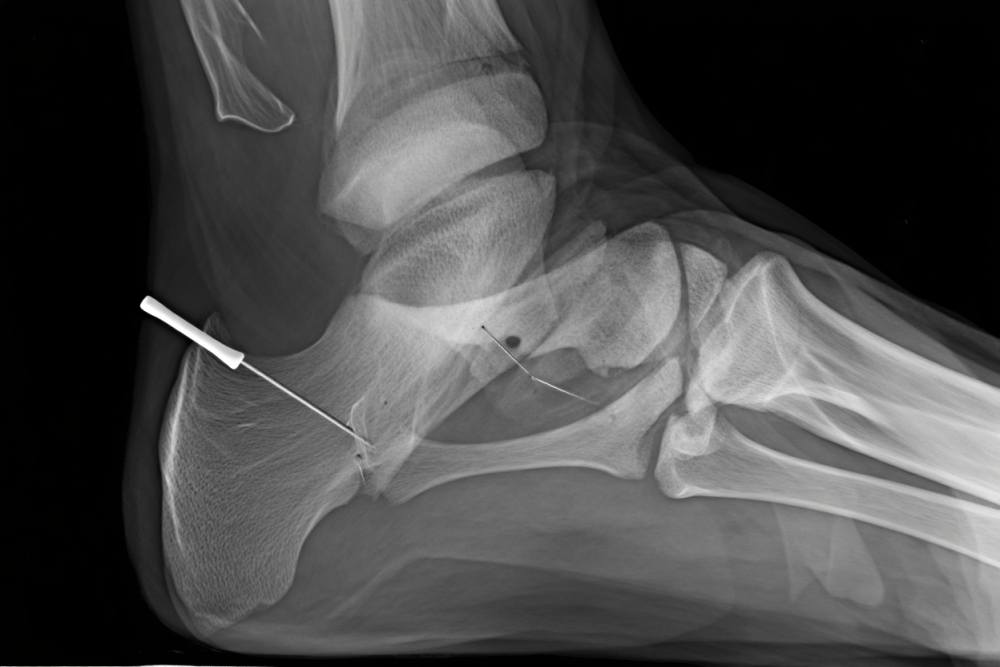

- L’imagerie médicale constitue l’étape décisive. La radiographie standard est généralement le premier examen réalisé, elle permet de visualiser la plupart des fractures malléolaires. Dans certains cas plus complexes, votre médecin pourrait prescrire un scanner ou une IRM pour mieux visualiser les fragments osseux ou évaluer les lésions des tissus mous environnants.

La technique la plus courante consiste à réaligner les fragments osseux puis à les fixer à l’aide de vis, plaques ou broches. Cette procédure, appelée ostéosynthèse, permet une stabilisation optimale favorisant la consolidation osseuse.